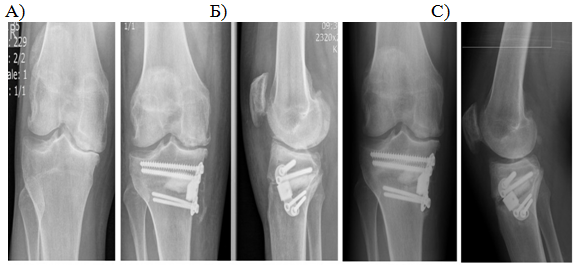

When studying the radiographs in the direct and lateral projections, disclosure of the joint gap was noted 3 months after the operation. Progression of medial compartment OA after a year did not occur, degenerative changes in another compartments were also absent (Figure 2) (Figure 3).

Figure 3 Patient M., 54 years old, rheumatoid arthritis. 2-nd stage secondary OA of the right knee. Before surgery (A), after 3 months (B), and a year (C) after surgery.